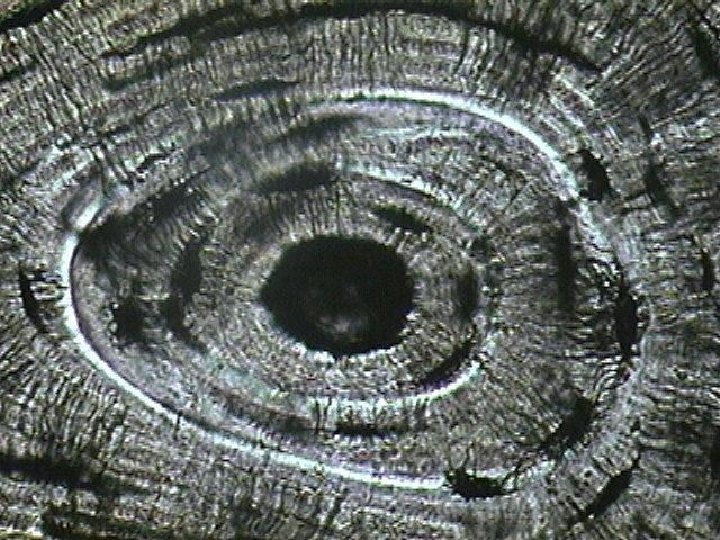

What is microscopic structure of bone: compact bone? l Haversian system, or osteon – the structural unit of compact bone – Lamella – weight-bearing, column-like matrix tubes composed mainly of collagen – Haversian, or central canal – central channel containing blood vessels and nerves – Volkmann’s canals – channels lying at right angles to the central canal, connecting blood and nerve supply of the periosteum to that of the Haversian canal

Microscopic Structure of Bone: Compact Bone – Osteocytes – mature bone cells – Lacunae – small cavities in bone that contain osteocytes – Canaliculi – hairlike canals that connect lacunae to each other and the central canal

Microscopic Structure of Bone: Compact Bone Figure 6. 5 a, b